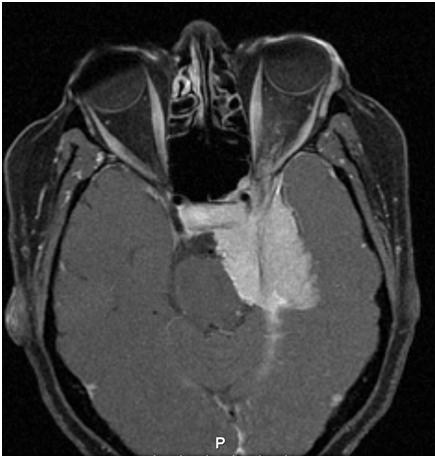

Diagnostic Imaging

Imaging of sphenoid wing meningiomas demonstrates a thick homogenous tumor bed with relative sparing of anatomic structures. The tumors are slow growing and have a tendency to conform around structures and cause compression rather than tissue invasion. The average annual growth rate of meningiomas are 1–3 mm per year.[11] On CT, meningiomas are isoattenuating to slightly hyperattenuating and exhibit homogenous and intense enhancement after injection of iodinated contrast. On MRI imaging, T1- and T2-weighted sequences have variable signal intensity, but they enhance intensely and homogeneously after injection of gadolinium. They also tend to exhibit hyperostosis and calcifications which can be seen on either CT or MRI imaging. Additionally, the presence of a dural extension (also known as a dural tail) is helpful in distinguishing a meningioma from fibrous dysplasia.[4][6][1][2]